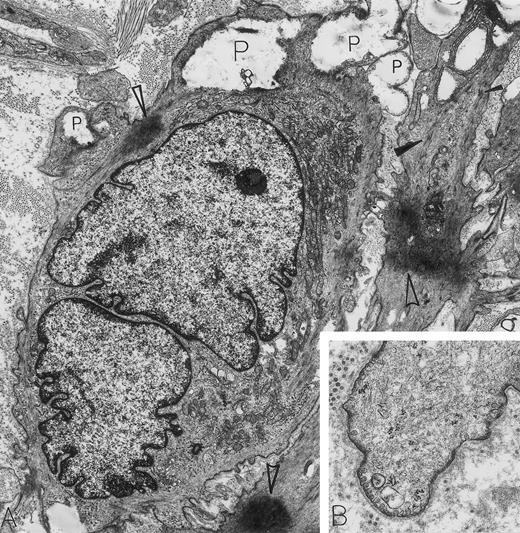

Leiomyosarcoma. A 56-year-old woman presented with abdominal pain and a 30-lb weight loss; a retroperitoneal mass was found. By electron microscopy, all features diagnostic for a metastatic leiomyosarcoma were present. These include caveolae, basal lamina, attachment plaques (all best seen at higher magnification in B), and bundles of microfilaments with dense bodies enclosed (closed arrowheads in A). Additional features of these spindle-shaped tumor cells of smooth muscle cell origin include large electron-dense masses of contracted actin filaments (open arrowheads in A), blunt, club-shaped surface projections (seen at higher magnification in B) and electron-lucent cytoplasmic pools representing admixed glycogen and lipid (P). Note that strands of rough endoplasmic reticulum are not dilated and are inconspicuous in these leiomyosarcoma cells displaying primarily a contractile phenotype. The light microscopic immunoperoxidase profile was positive for vimentin, muscle-specific actin and desmin, and negative for S-100, neurofilament, keratin, and α-1-antitrypsin for this tumor. (A) Original magnification × 8,000; (B) Original magnification × 24,000. (Courtesy of Ann M. Dvorak, MD, Department of Pathology, Beth Israel Deaconess Medical Center, 330 Brookline Ave, Boston, MA 02215.)